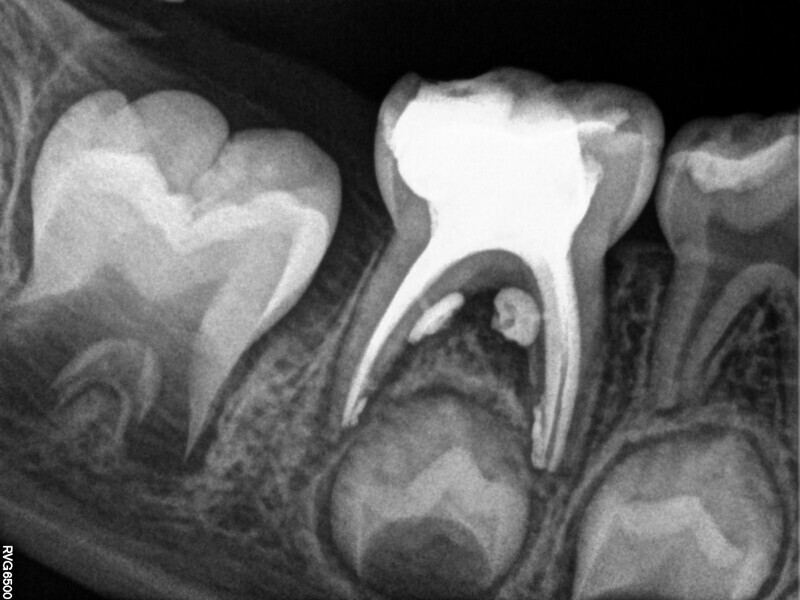

Cas 3 (Figs. 10 à 13)

Ce patient âgé de 7 ans présentait une douleur légère depuis plusieurs jours. L’examen a montré une lésion cavitaire étendue et profonde dans la première molaire temporaire inférieure gauche. La gencive ne présentait aucun gonflement, mais la dent était douloureuse à la percussion. La radiographie a confirmé la gravité de la carie, mais n’a révélé aucun signe correspondant à une modification de l’os environnant. Une pulpectomie était le traitement de choix. Le diagnostic de nécrose pulpaire a été confirmé après la préparation de la cavité d’accès et l’identification de trois canaux qui ont alors été complètement négociés.Lors d’un second rendez-vous, 15 jours plus tard, la dent était totalement asymptomatique et elle a été restaurée au moyen d’une couronne en acier inoxydable. À la visite de suivi à 36 mois, la dent présentait une fonction normale et était totalement saine.